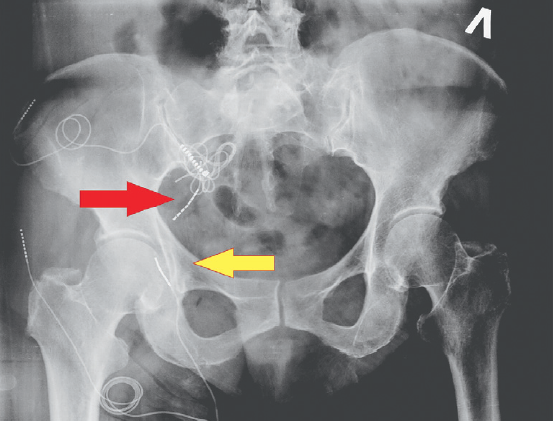

A day after the surgery, X-ray control of the position of the electrodes was conducted (Fig. 5).

Fig. 5. X-ray of patient N. one day after implantation of the electrode to the root of S3 (red arrow) and the electrode to the pudendal nerve on the right (yellow arrow)

Рис. 5. Рентгенограмма пациентки Н. через сутки после имплантации электрода к корешку S3 (красная стрелка) и электрода к половому нерву справа (желтая стрелка)